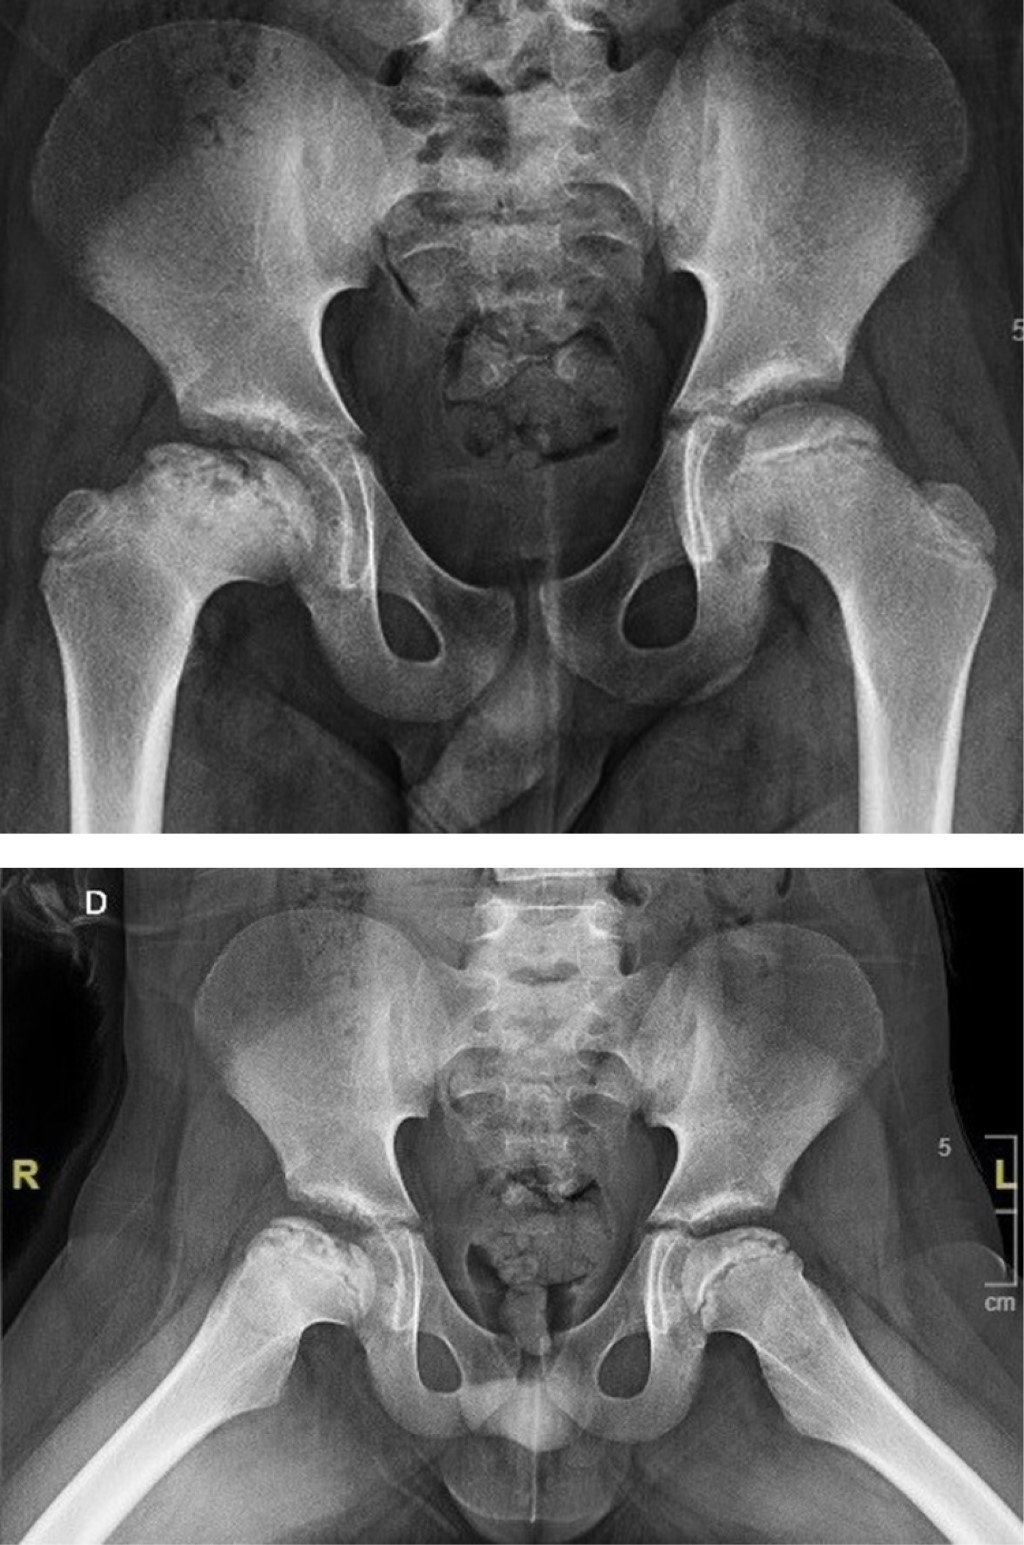

Treatment of femoroacetabular impingement with controlled dislocation of the hip

The femoroacetabular impingement is a syndrome caused by abnormal contact between the femoral head and the acetabulum; it can progress in complications, and the treatment must be individualized with the aim to restore the functionality of the joint. A case of a 12 years old patient who presented clinical findings about impingement, he has history Perthes disease. We performed a surgical hip dislocation technique with femoroplasty. We obtained good results. The clinical and radiographic characteristics of the patient has described and the case resolution.

Figure 1

Figure 2